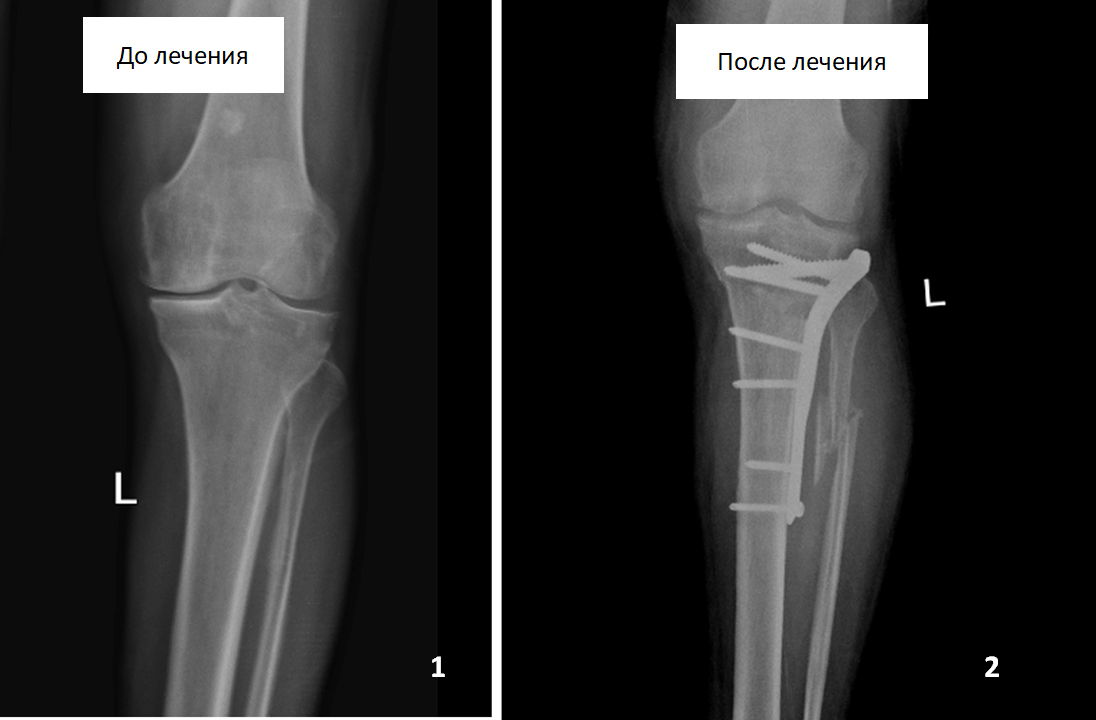

Мужчина обратился за помощью с жалобами на боли в области левой голени и левого коленного сустава. Во время консультаций в других медицинских учреждениях пациенту было предложено выполнить протезирование левого коленного сустава, от которого он отказался.

После проведения обследований была выявлена установочная варусная деформация левой голени и выполнена корригирующая резекция левой большеберцовой кости, в результате которой ось кости была восстановлена.

В настоящее время боли пациента не беспокоят, он полноценно пользуется конечностью в течение трех лет после операции.